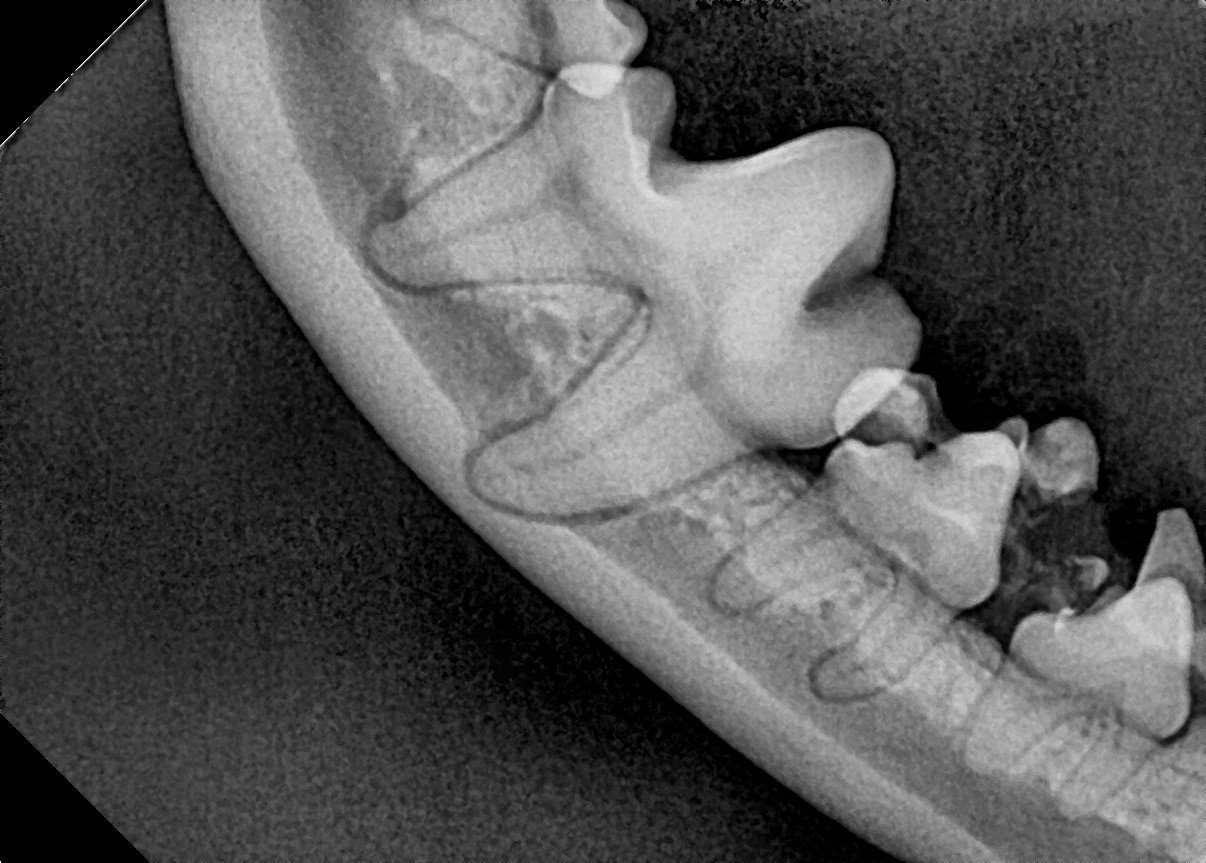

잔존 유치를 제거해 주었더니 별다른 교정 장치를 사용하지 않았음에도 2주 후 제위치로 이동하고 있는 송곳니를 확인할 수 있습니다.